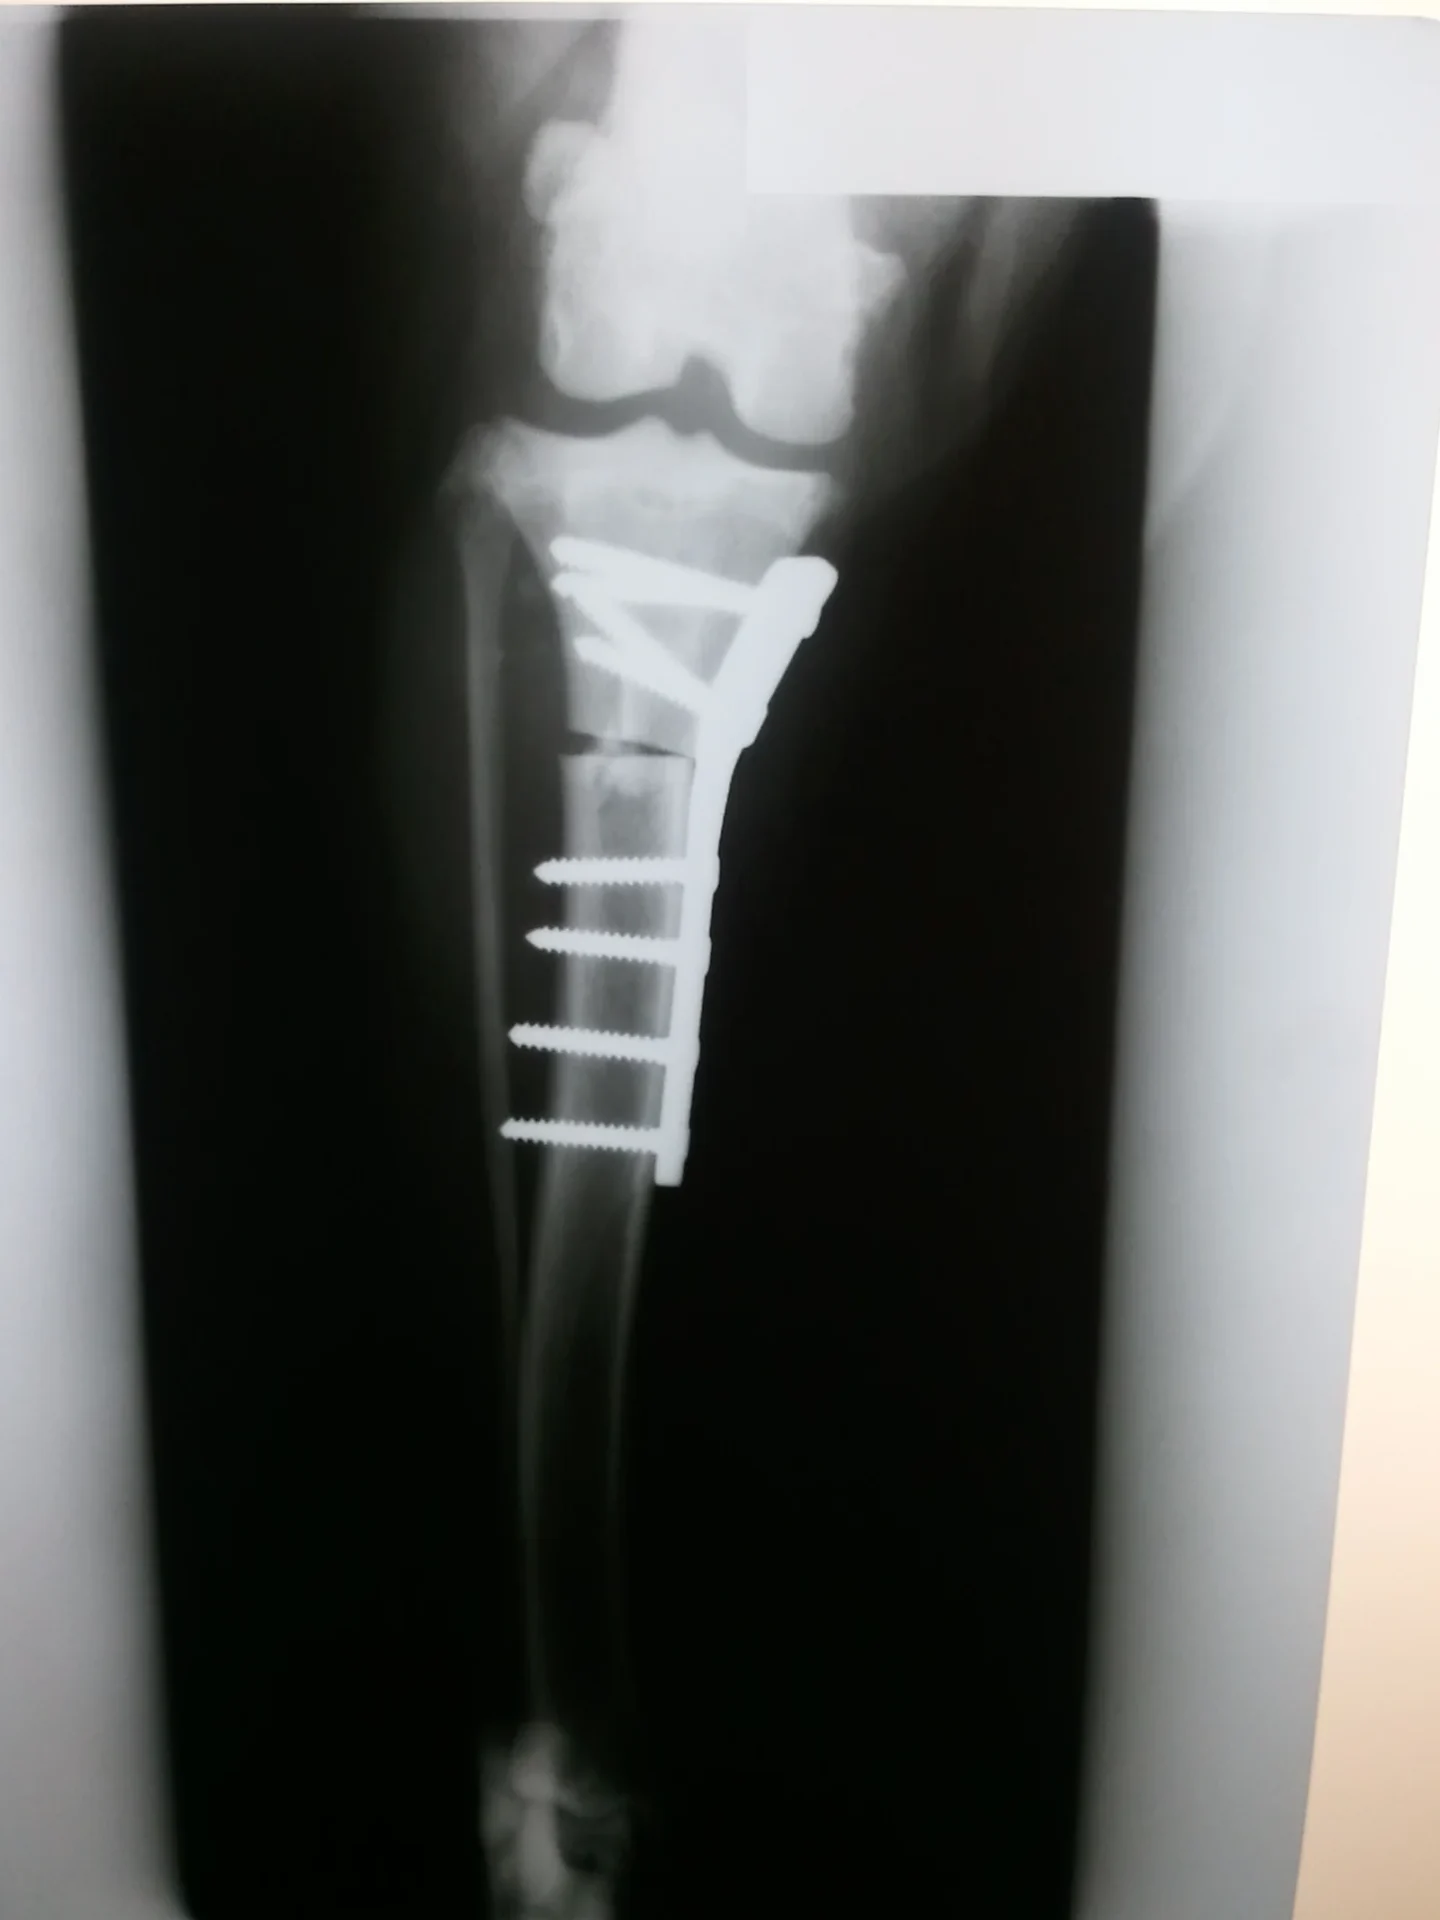

Galería de casos clínicos

Casos clínicos de cirugía (tejidos blandos, traumatología, neurocirugía, artroscopia)